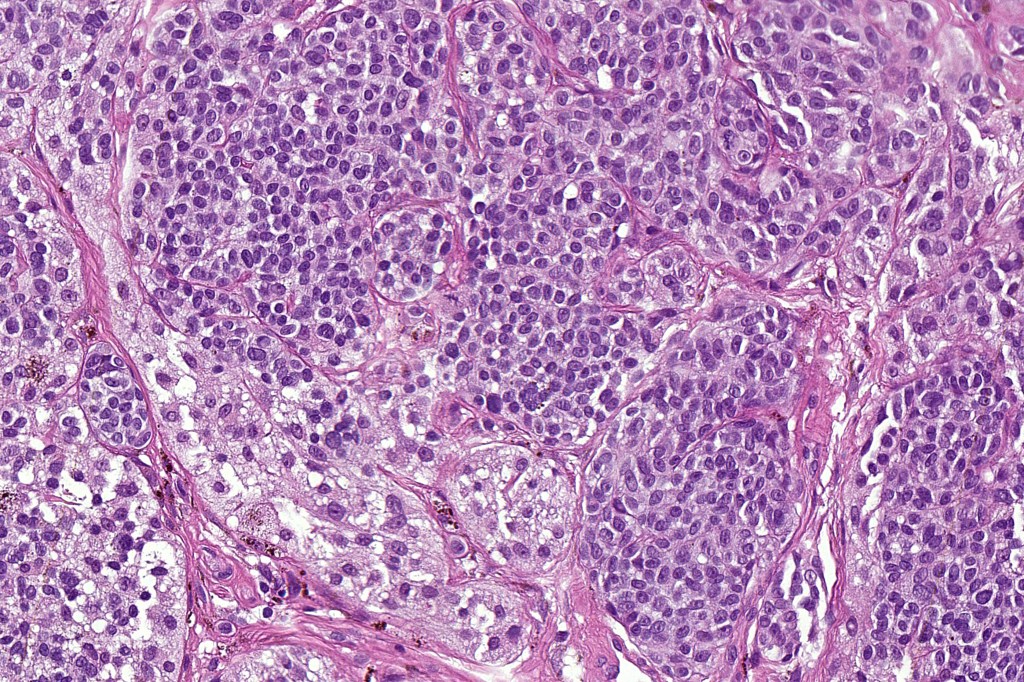

Histological features

•Nuclei vesicular or hyperchromatic

•Pleomorphism is not generally marked and indeed can be very subtle

•Variable mitotic activity